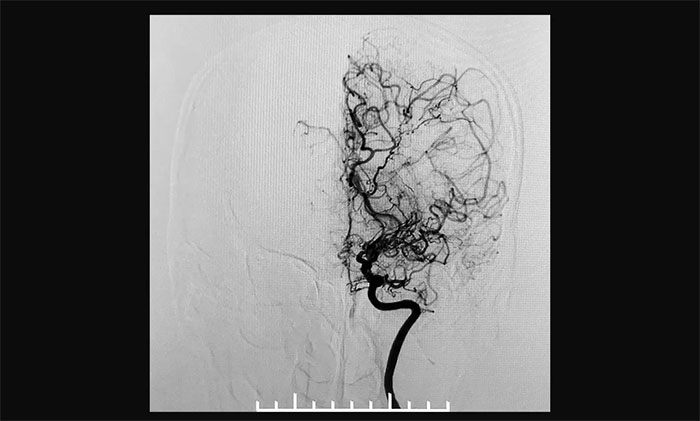

上海蓝十字脑科医院神经外科6A病区专家宫卫东主任介绍,烟雾病又称“自发性脑底动脉环闭塞症”,是一组以双侧颈内动脉末端和(或)大脑前动脉、大脑中动脉起始部缓慢进展性狭窄以致闭塞后,脑底出现代偿性异常血管网为特点的脑血管病,因其血管造影形似“烟雾”,故称为“烟雾病”。

▲异常血管网在脑血管造影时形似“烟雾”

近年来,随着经颅多普勒超声、CT、磁共振以及数字减影血管造影(DSA)等影像学技术的逐渐发展和普及,在我国,烟雾病不再罕见,确诊率也呈逐年增高的趋势。